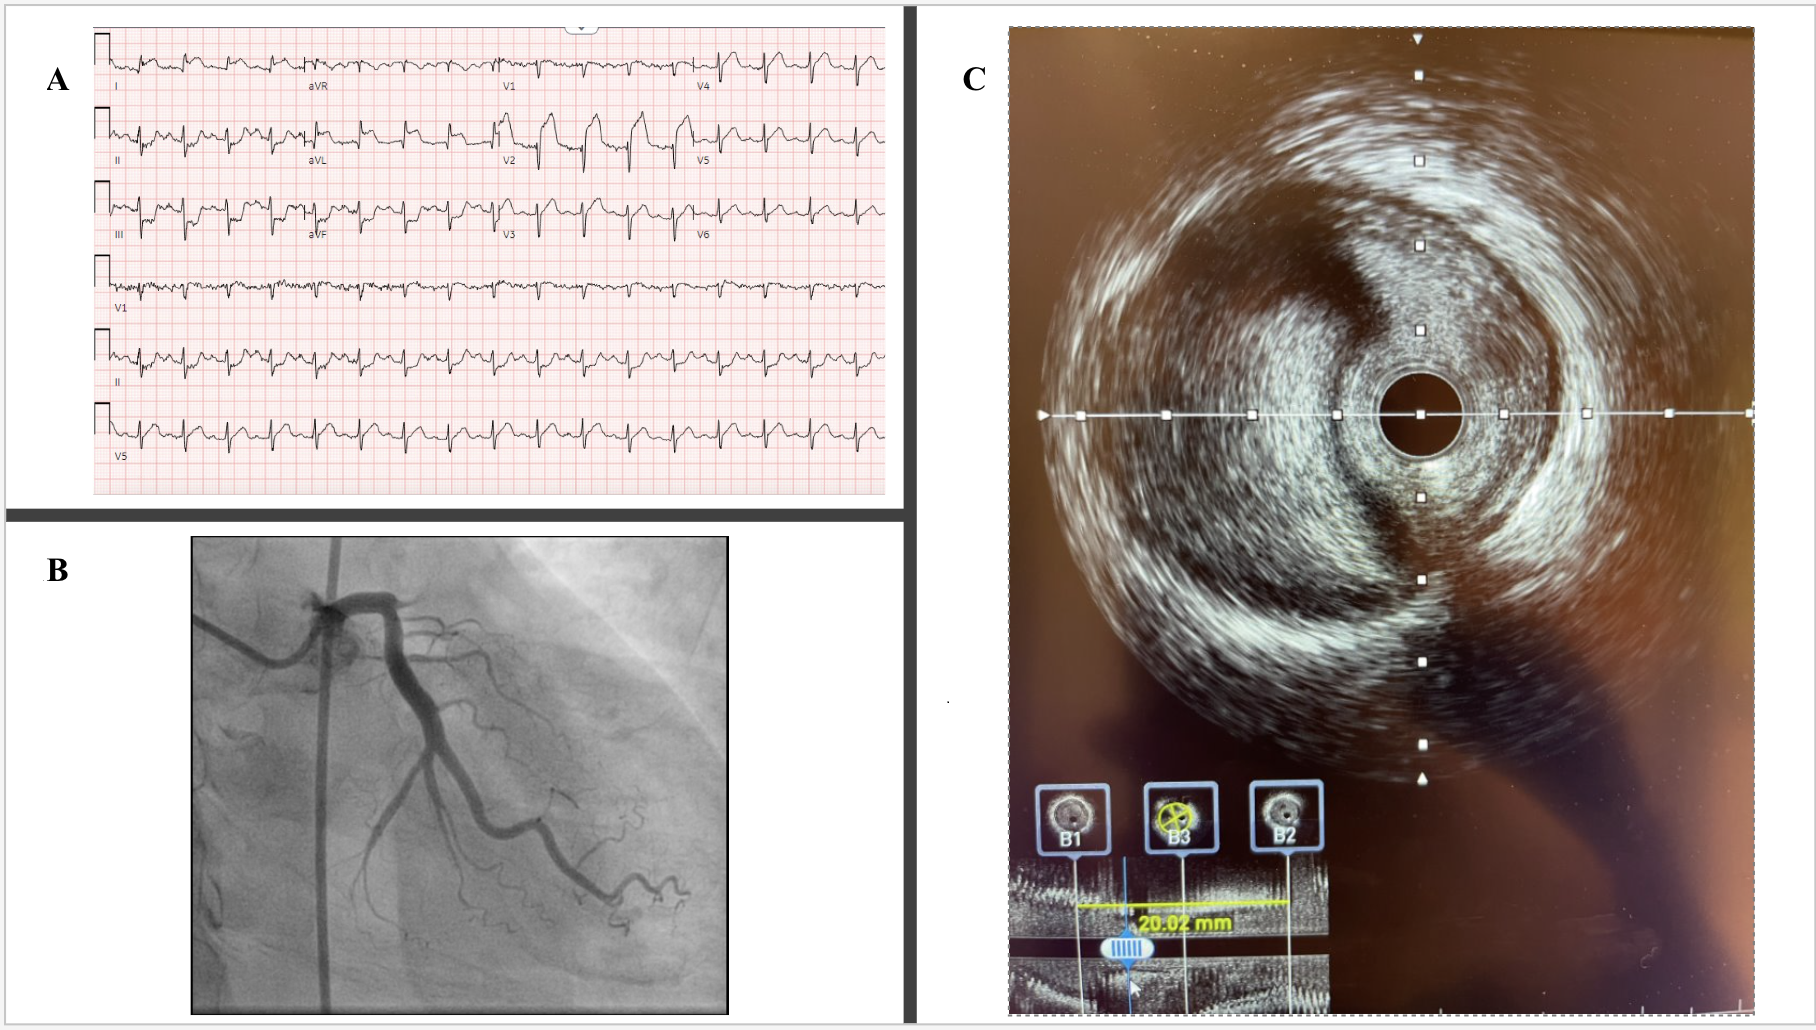

A 54-year-old man presented following a motor vehicle crash that resulted in a subarachnoid hemorrhage (SAH). Electrocardiogram showed anterolateral ST-segment elevations (Figure A). Troponin I was elevated at 3.19 ng/mL, and echocardiogram showed an antero-apical wall-motion abnormality with an ejection fraction of 20% to 25% (Video 1). Anticoagulation and dual antiplatelet therapy for acute coronary syndrome (ACS) were initially withheld given concern for SAH expansion. However, within 8 hours, troponin I rose to 87.20 ng/mL.

After discussion with the neurosurgical team, mono-platelet therapy with 81 mg of aspirin was initiated, and cardiac catheterization was performed via the right femoral artery. Angiography revealed an occluded ostial left anterior descending artery (LAD) (Figure B, Video 2). Given these findings, the patient was given 7000 units of unfractionated heparin and loaded with 600 mg of clopidogrel. The lesion was readily crossed with a wire and dilated with a compliant balloon, restoring Thrombosis in Myocardial Infarction-2 flow and revealing a 95% ostial-to-proximal LAD diffuse stenosis (Video 3). Intravascular ultrasound imaging demonstrated compression of the vessel lumen by an intramural hematoma, confirming a traumatic dissection (Figure C, Video 4). A cutting balloon was used to fenestrate the false lumen. Flow improved but remained suboptimal angiographically; thus, a single drug-eluting stent was deployed (Video 5). Dual-antiplatelet therapy (DAPT) with the addition of 75 mg of clopidogrel daily was started, with no further neurologic sequelae. Post-procedure echocardiogram showed a persistently reduced ejection fraction of 25% to 30%. Guideline-directed medical therapy (GDMT) was initiated, and the patient was discharged home with DAPT for 1 year followed by aspirin monotherapy thereafter. At follow-up in the cardiology clinic, the patient had been tolerating GDMT well and denied experiencing any subsequent angina.

The incidence of traumatic coronary artery dissection due to chest wall trauma is rare, with reported estimates as low as 0.1%.1 It is believed that the sudden dissipation of kinetic energy from the body smashing into an immobile object results in the shearing of the vessel layers.2 Intravascular imaging can prove key in making the diagnosis of traumatic dissection.3 Cutting balloon therapy might reduce the risk of hematoma propagation during stenting. Multidisciplinary collaboration allowed for the management of concurrent traumatic ACS and intracranial bleeding in this trauma patient.